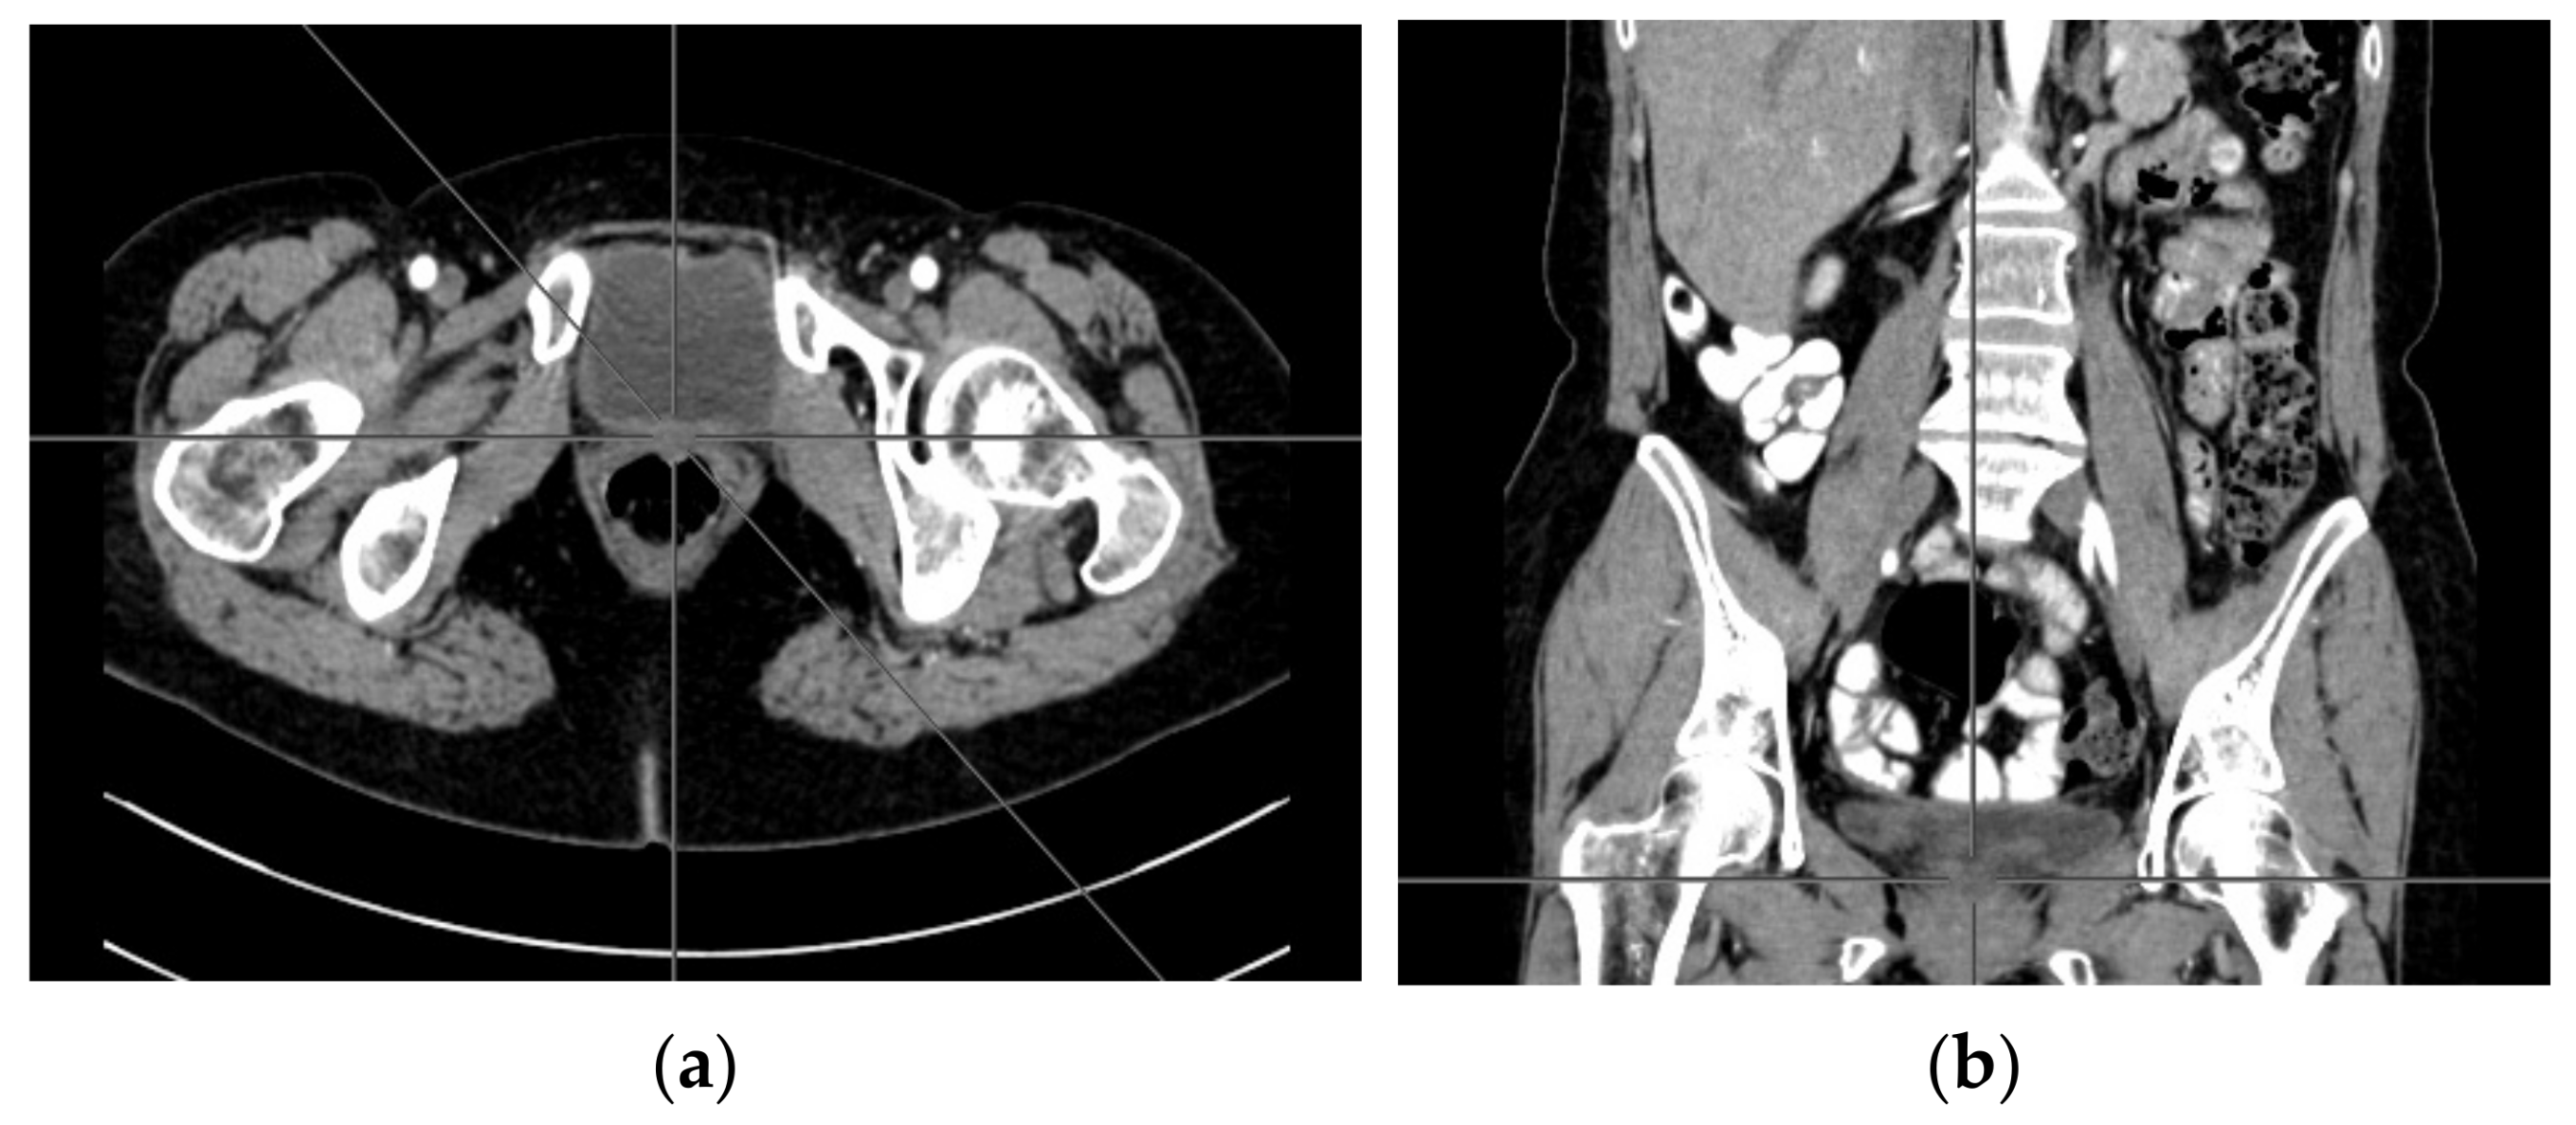

2. Case Report